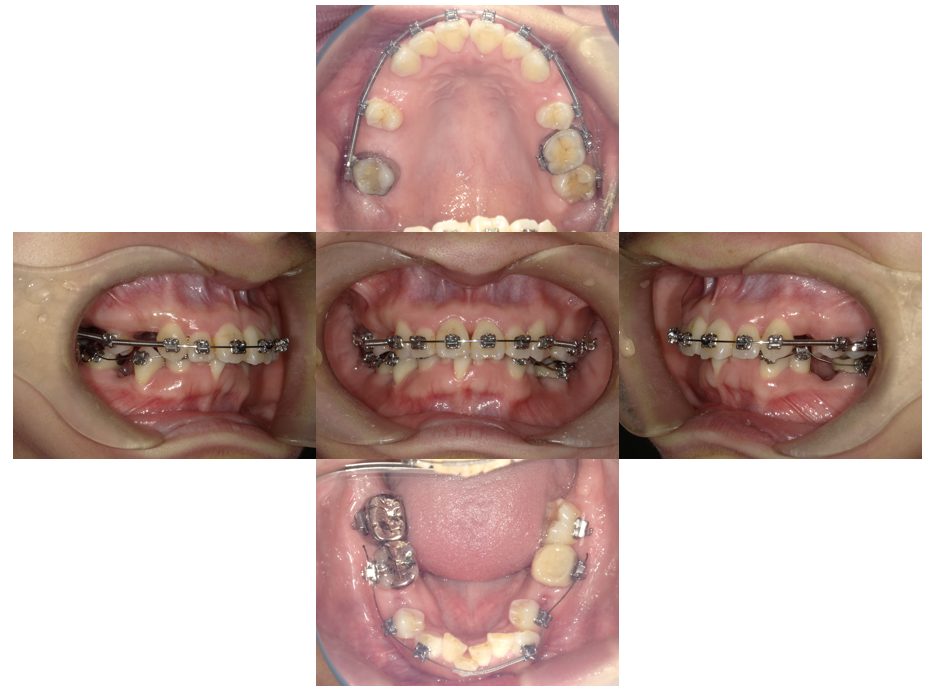

外科矯正治療・インプラント治療の症例紹介(三隅歯科クリニック)

三隅 賢祐(三隅歯科クリニック)

症例詳細

| 主訴 | 20代女性 矯正治療希望。治療途中の歯もあるので治したい。左顎関節が痛い。 |

| 治療内容 | 矯正治療を行いました。 |

| 治療費 | 1,400,000円(税込み) |

| 治療期間 | 3年(矯正治療期間 2年半) |

| 治療回数 | 40回 |

| 想定されたリスク | 顎骨の変形があったので、全身麻酔下による外科処置が必要になり、身体的、精神的負担が増す可能性がありました。 清掃状況によっては矯正中にむし歯が発生するリスクがありました。 |